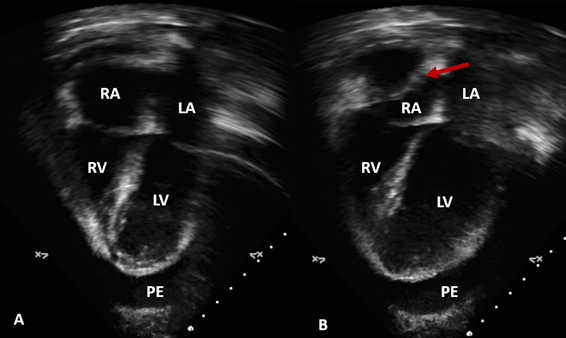

Figure 2 Echocardiogram, Apical 4 chamber view. (A) Images of the four cardiac chambers during ventricular systole, with right atrial cavity within normal range. (B) Bulging of the right atrial wall ceiling (red arrow) during final ventricular diastole. RA, right atrium; LA, left atrium; RV, right ventricle; LV, left ventricle; PE, pericardial effusion